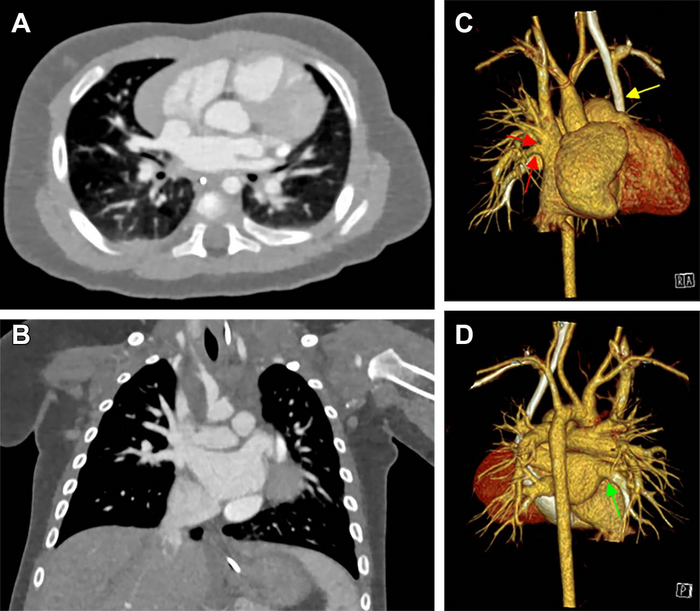

Congenital heart defects are the leading cause of morbidity and mortality in the neonatal period, occurring in up to one percent of live births. Of those, approximately 25% are critical defects requiring surgical intervention within the first month after birth. A comprehensive assessment, including ultrasound, MRI and CT exams, is typically needed to plan for surgery and to create virtual and printed 3D reconstructions of the heart.

PCCT is an emerging imaging technique that counts the exact number and measures the energy of incoming x-ray photons. Compared with DSCT technology, PCCT offers higher image resolution and/or reduced radiation doses, which is of particular interest when imaging children. The PCCT technique has already been shown to improve cardiovascular CT imaging in adults. However, data on neonates and small children are lacking.

The researchers found that the PCCT images were sharper, with less image noise and greater contrast than DSCT images. The mean overall visual image quality ratings were higher for PCCT versus DSCT at a similar radiation dose. More than 97% of the PCCT images were at least diagnostic quality, compared to 77% of the DSCT images.

“PCCT is a promising method that may improve diagnostic image quality and efficiency compared to DSCT imaging,” Dr. Dirrichs said. “This higher efficiency can be used to reduce the radiation dose at a given image quality level or to improve image quality at a given radiation level.”